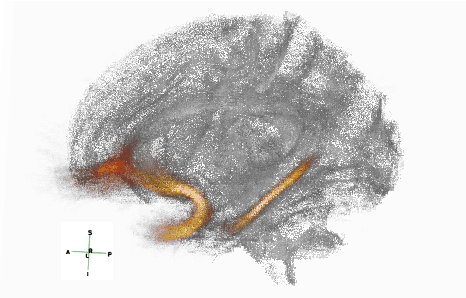

Abstract:Post-traumatic epilepsy (PTE) is a life-long complication of traumatic brain injury (TBI) and is a major public health problem that has an estimated incidence that ranges from 2%-50%, depending on the severity of the TBI. Currently, the pathomechanism that in-duces epileptogenesis in TBI patients is unclear, and one of the most challenging goals in the epilepsy community is to predict which TBI patients will develop epilepsy. In this work, we used diffusion-weighted imaging (DWI) of 14 TBI patients recruited in the Epilepsy Bioinformatics Study for Antiepileptogenic Therapy (EpiBioS4Rx)to measure and analyze fractional anisotropy (FA), obtained from tract-based spatial statistic (TBSS) analysis. Then we used these measurements to train two support vector machine (SVM) models to predict which TBI patients have developed epilepsy. Our approach, tested on these 14 patients with a leave-two-out cross-validation, allowed us to obtain an accuracy of 0.857 $\pm$ 0.18 (with a 95% level of confidence), demonstrating it to be potentially promising for the early characterization of PTE.